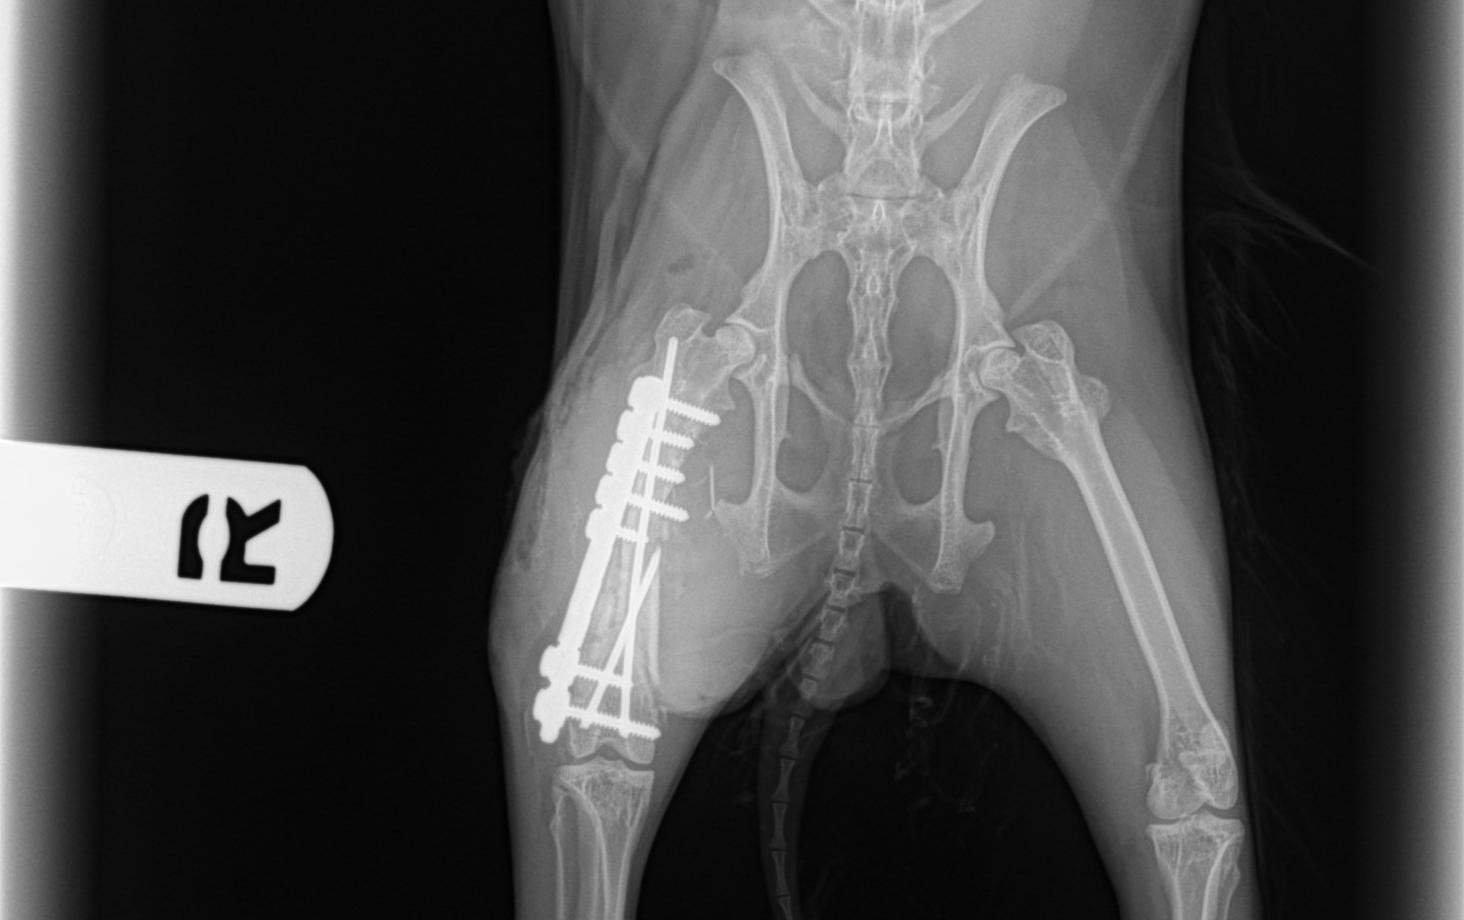

X-rays revealed the diagnosis: her femur (thigh bone) was shattered.

I was called to the Animal Clinic of Morris Plains to fix the fracture. The repair involved using a tiny plate, 7 screws and 2 pins.

The bone was smaller than a pencil…